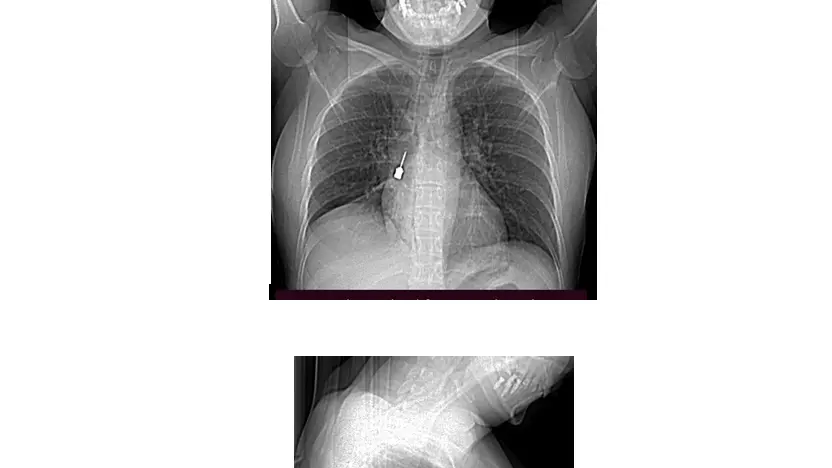

La paziente è giunta al Pronto Soccorso del G.O.M. esibendo un esame di diagnostica per immagini (Tomografia Computerizzata) eseguito a causa di una tosse persistente e di un forte dolore a livello toracico. La TC mostrava la presenza di un corpo estraneo metallico pericolosamente incastrato nel bronco lobare inferiore del polmone destro e un concomitante pneumomediastino, ossia la presenza di aria nello spazio compreso fra i due polmoni.